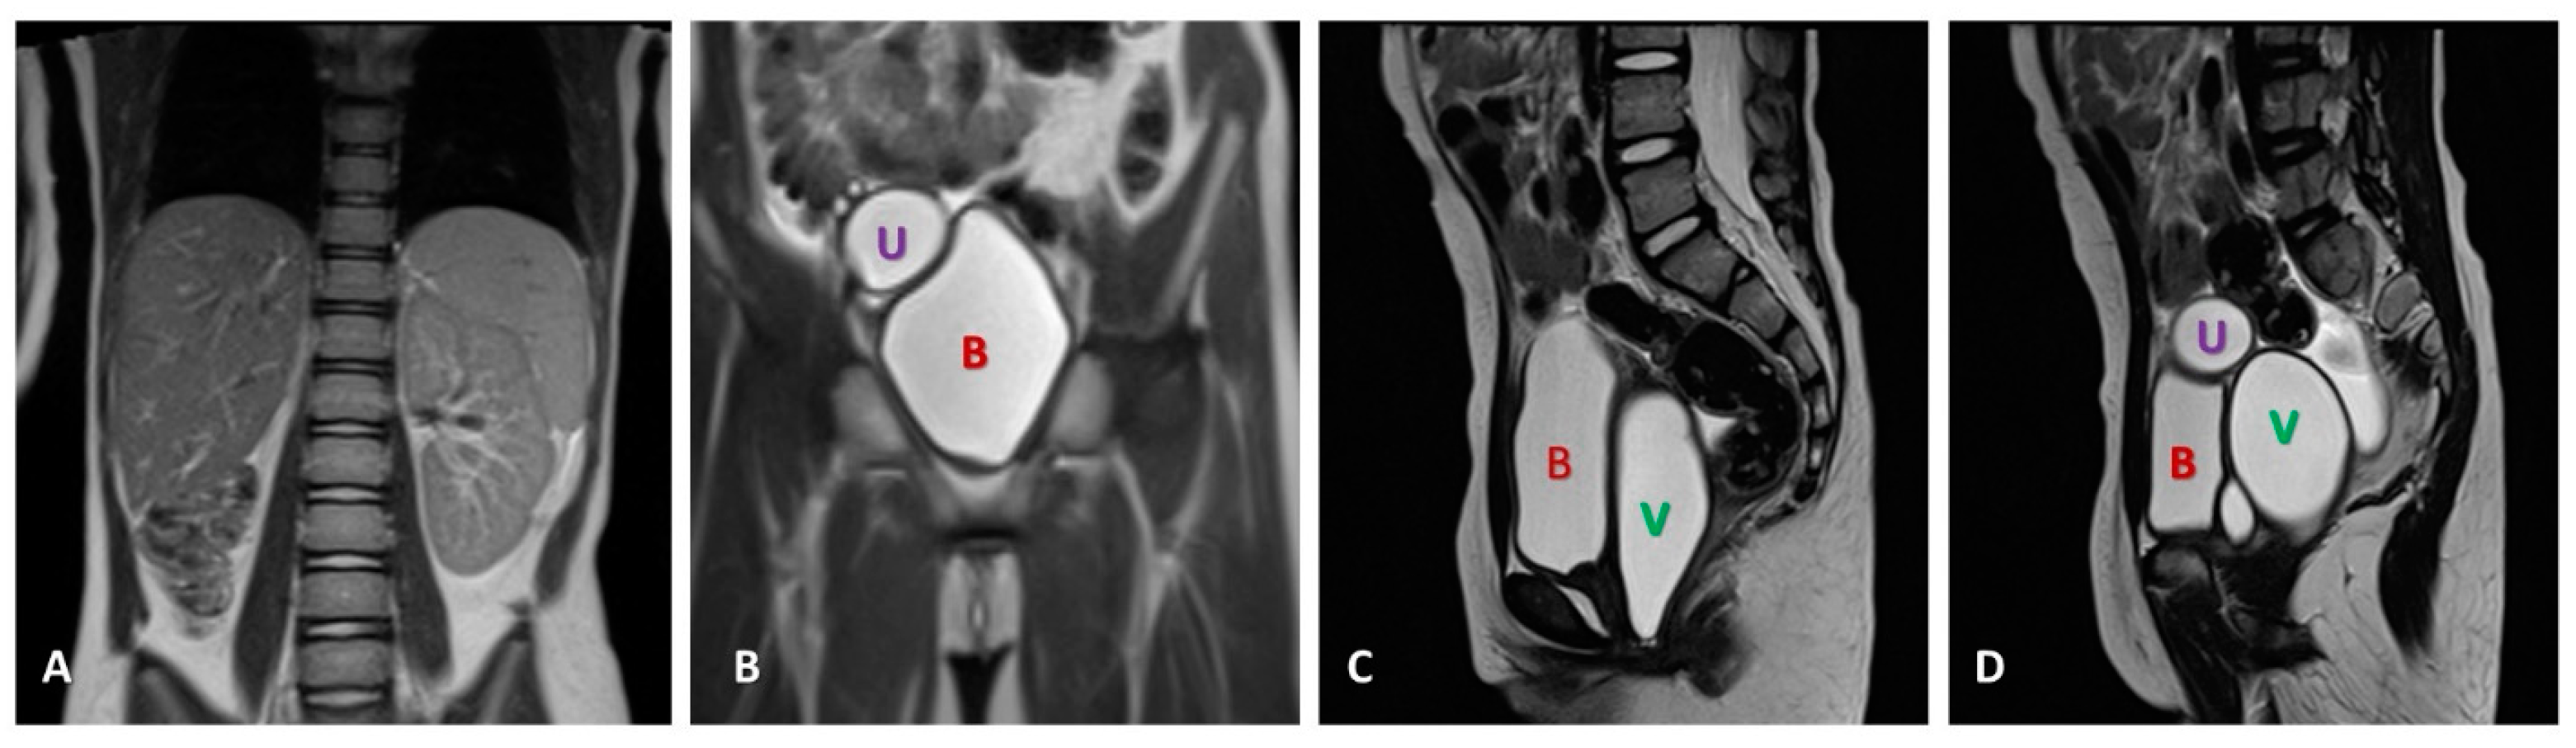

2. Case Presentation